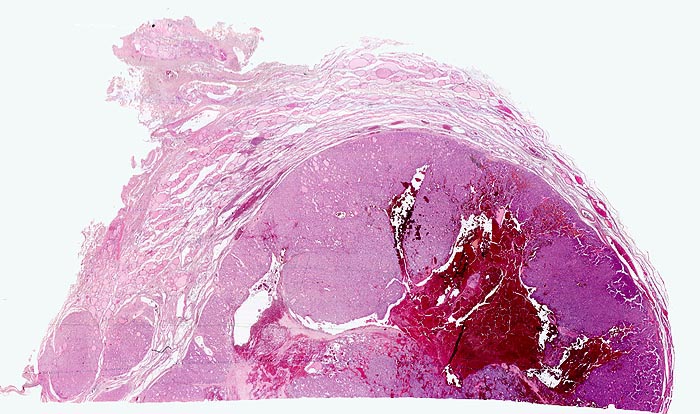

• Anschnitt eines grossen mikrofollikulären Knotens (autonomes Adenom) mit angedeuteter Kapsel und zentraler Einblutung. Oben zwei weitere kleine Satellitenknoten.

• Kompression des angrenzenden Schilddrüsenparenchyms. Dieses besteht aus grossen Follikeln mit kubischem oder abgeflachtem Epithel und reichlich kompaktem dunklem Kolloid in den Follikellumina.